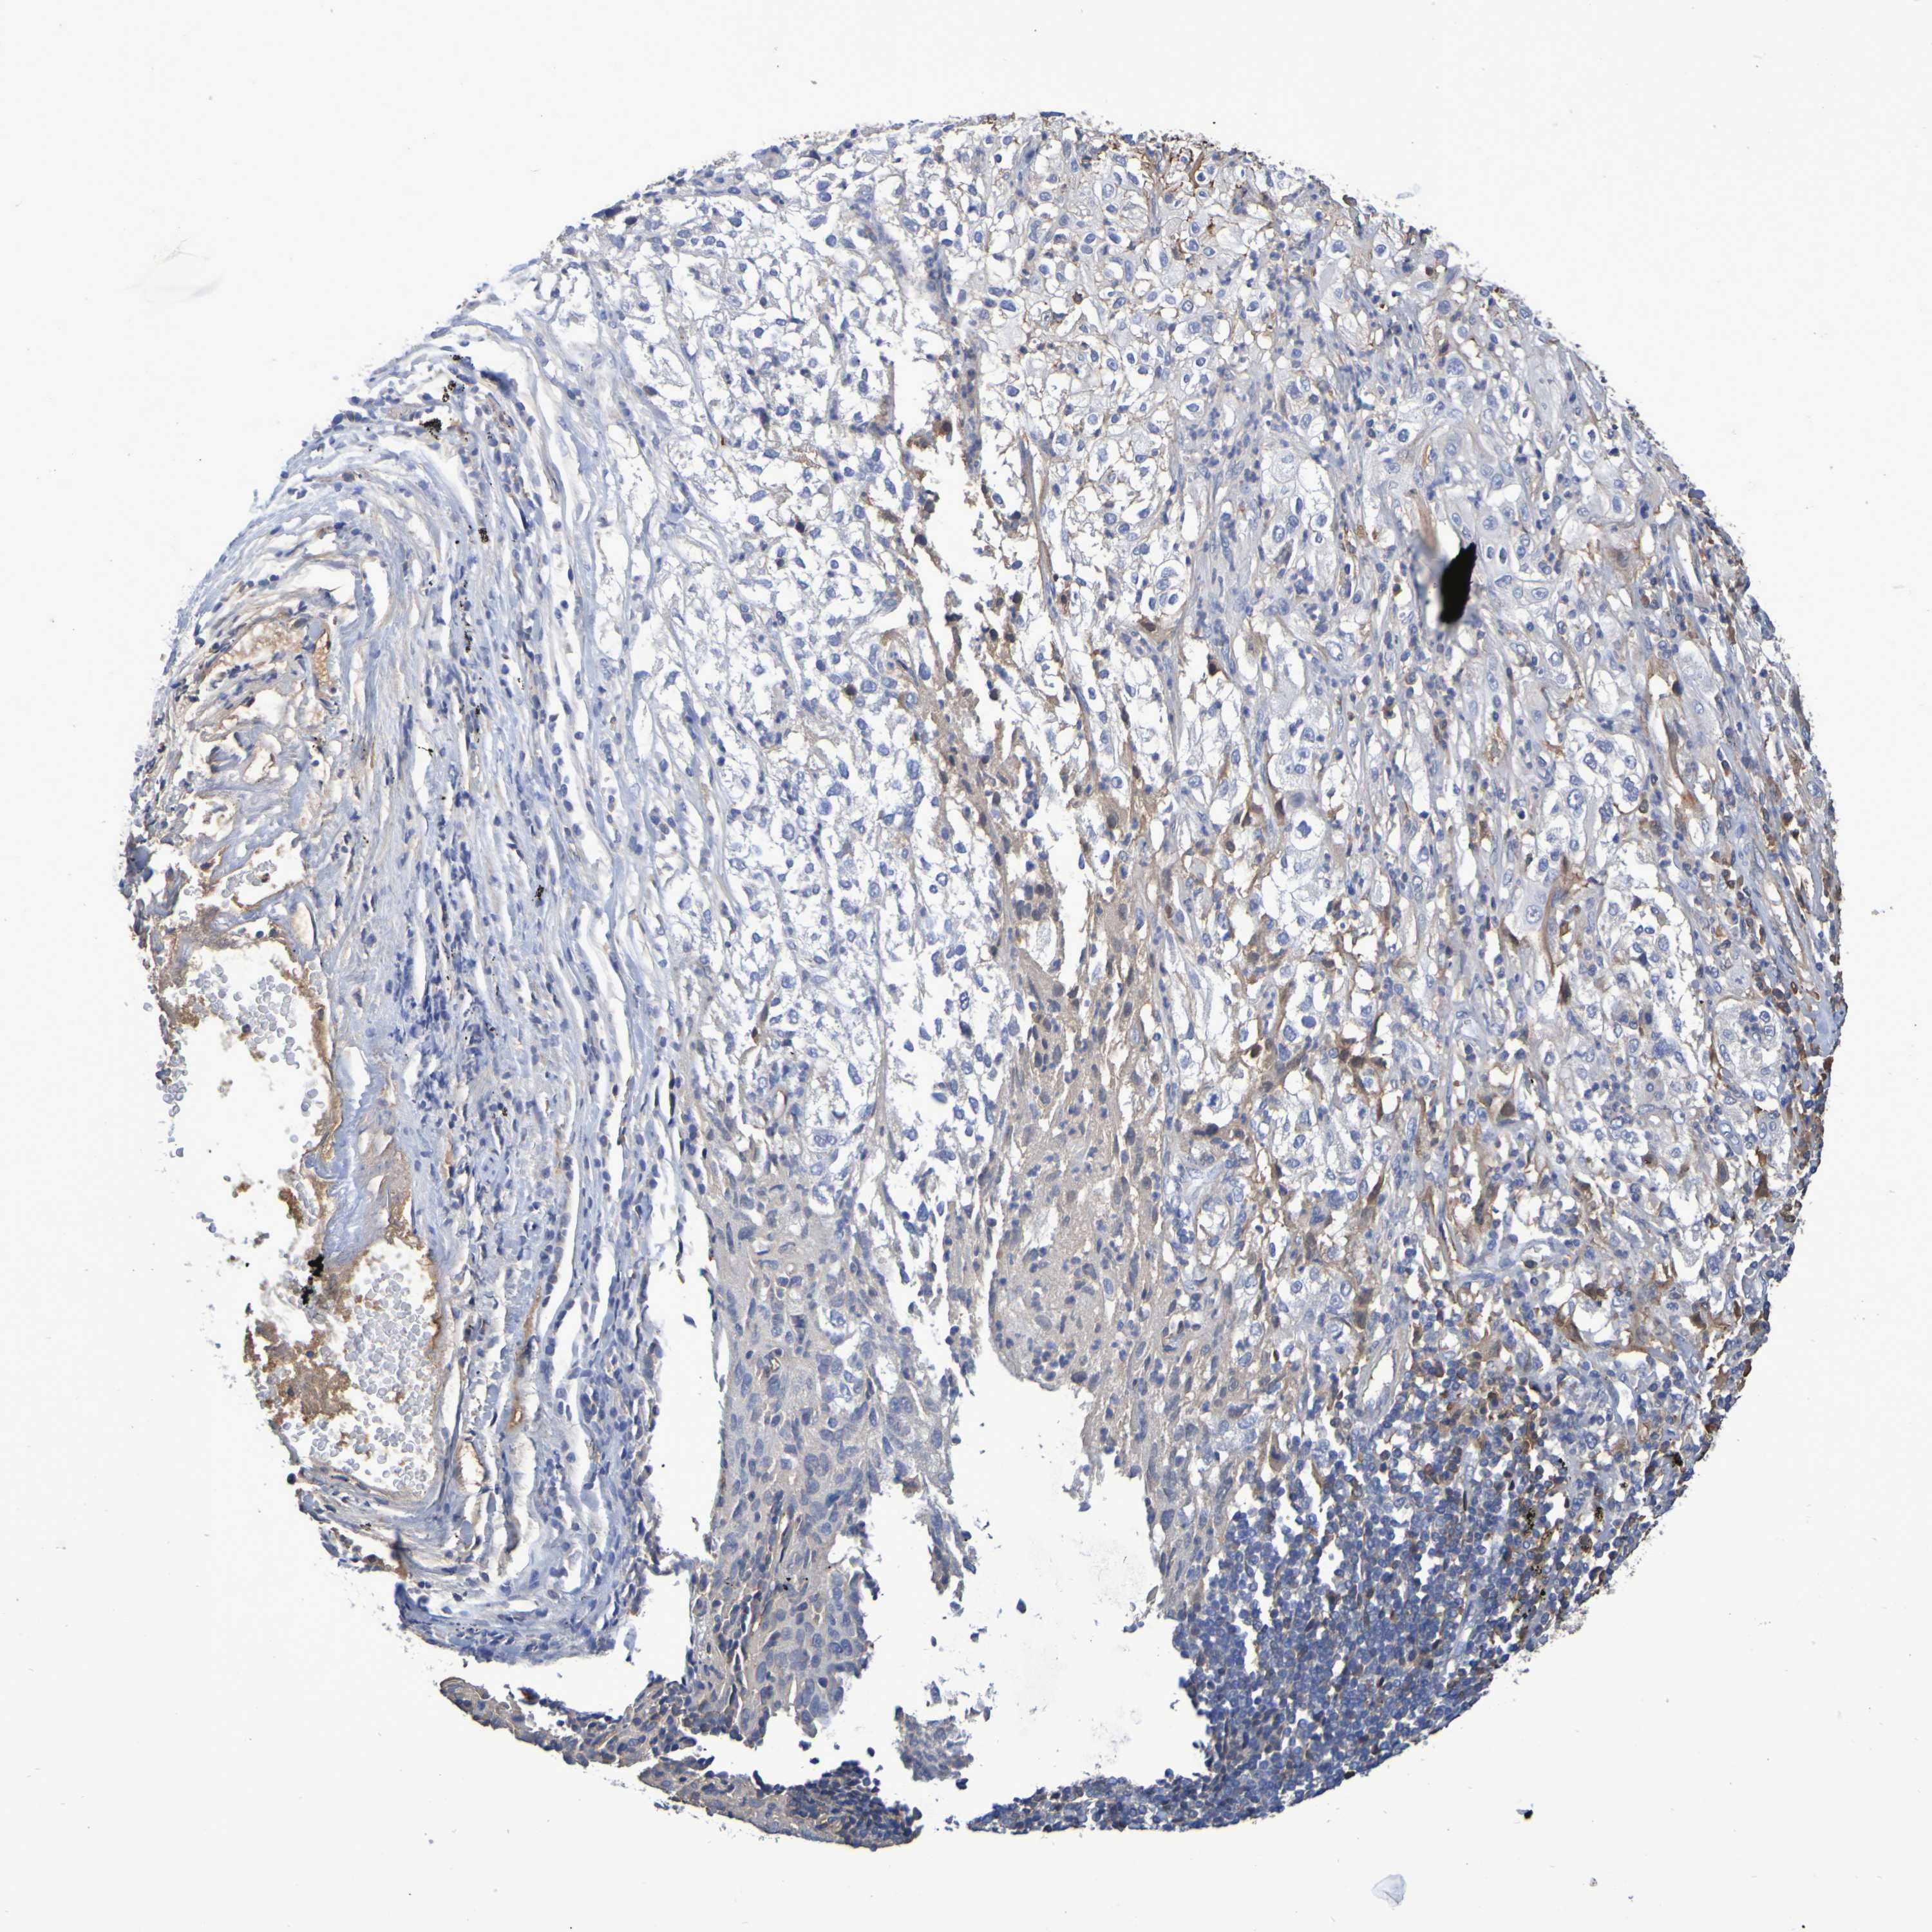

CANCER LUNG CANCER Show tissue menu

Lung cancer

Human cancer

GAB3 is potential prognostic, high expression is favorable in Lung Adenocarcinoma (TCGA)

GAB3 is not prognostic in Lung Adenocarcinoma (validation)

GAB3 is not prognostic in Lung Squamous Cell Carcinoma (TCGA)